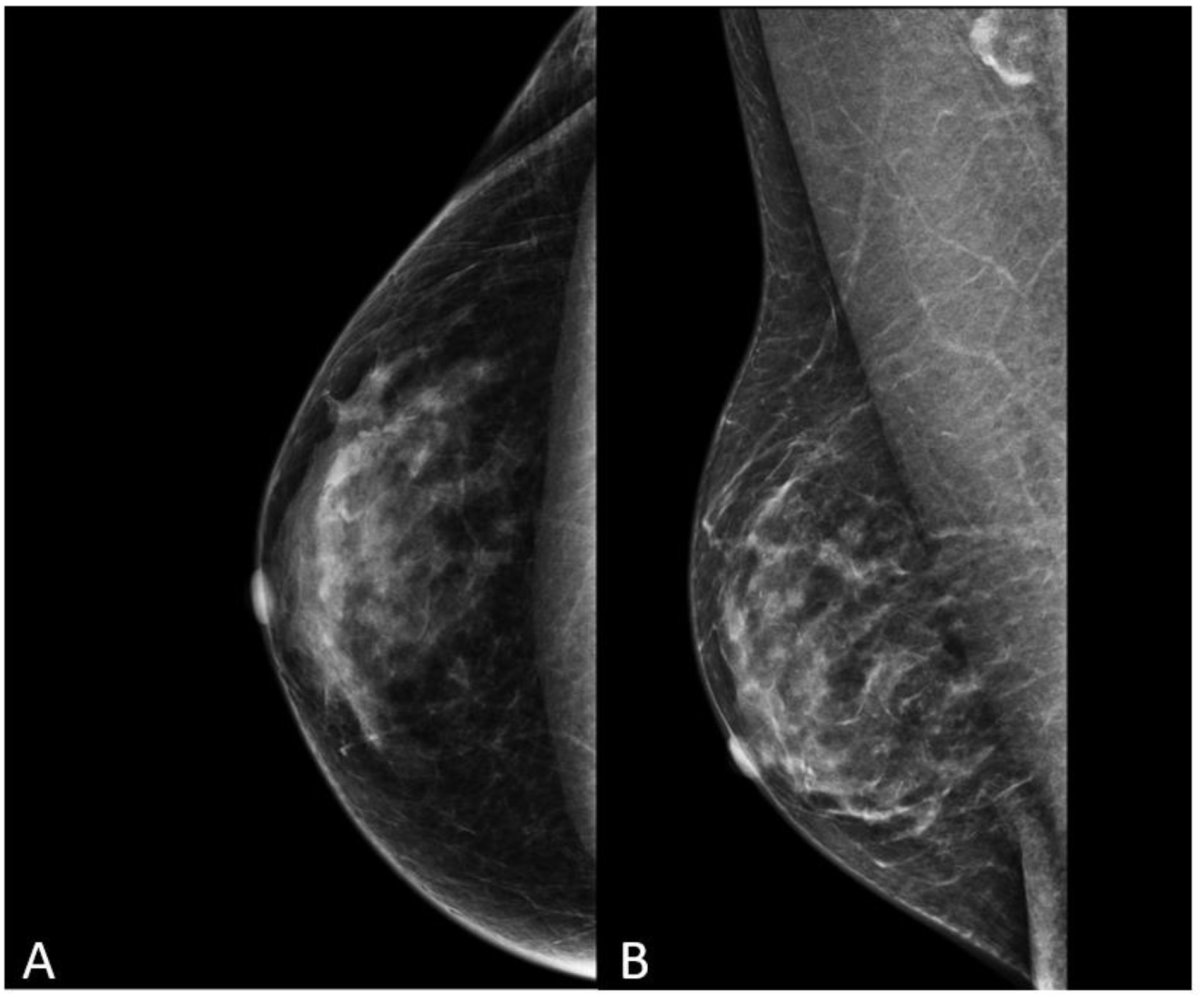

Image source: D’Angelo A, Portaluri A, Caprini F et al.: Male Breast: A Review of the Literature and Current State of the Art of Diagnostic Imaging Work-Up; Diagnostics 2023 (CC BY 4.0)

Anna D'Angelo from the Catholic University of the Sacred Heart in Rome addressed transgender breast imaging, emphasising the importance of correct terminology. Transgender, she clarified, is an umbrella term for people whose gender identity does not align with the sex assigned to them at birth, while cisgender describes people whose gender identity aligns with their birth-assigned sex.

D'Angelo focused on patients undergoing feminising and masculinising gender-affirming surgery and gender-affirming hormone therapy (GAHT). However, evidence of breast cancer risk in this population remains limited due to a lack of long-term follow-up, inadequate documentation of hormone exposure, and an absence of prospective studies.

Breast cancer screening for transgender individuals faces multiple challenges, D'Angelo noted. These include low participation in or awareness of screening programmes, lack of trust in healthcare professionals, and poor knowledge of screening guidelines among both the transgender population and healthcare providers. A lack of training and education among clinicians compounds the problem.